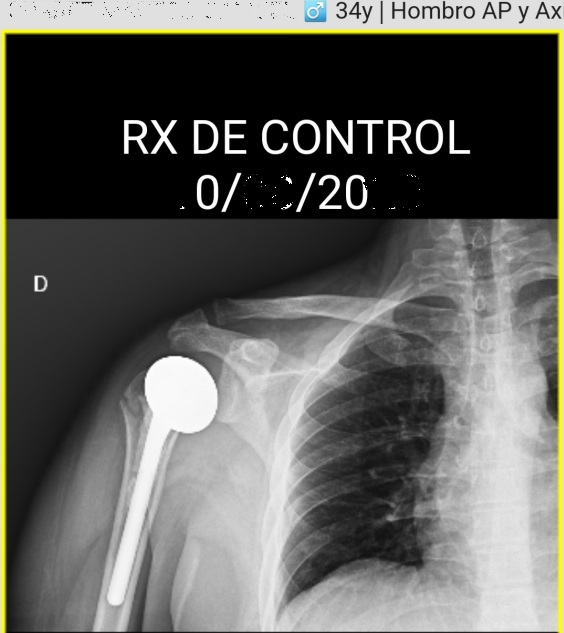

Las lesiones en un accidente de moto suelen ser más graves que en otros siniestros, y el caso de Samuel no fue la excepción. Tras el accidente comenzó un proceso médico durísimo que incluyó varias cirugías y una rehabilitación interminable.

La complicación más devastadora llegó con una infección por pseudomonas, que frenó su recuperación y puso en riesgo su salud de forma seria.